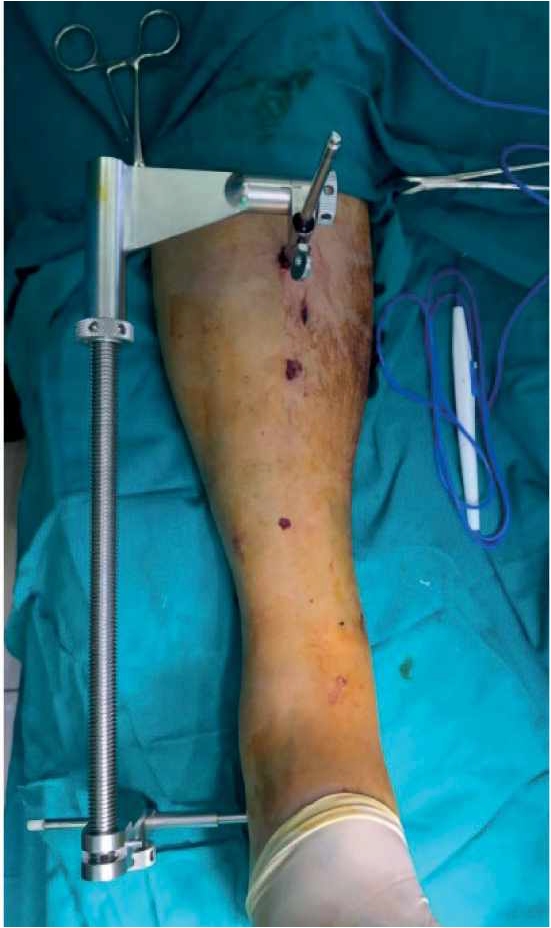

Операция выполнена следующим образом. Поврежденную нижнюю конечность уложили на рентгенопрозрачный стол таким образом, чтобы обеспечить возможность рентгеновской визуализации голени на всем протяжении. Предварительно установили дистрактор для осуществления первичной репозиции отлом-

ков и грубой коррекции оси сегмента. При этом детали дистрактора смонтировали таким образом, чтобы они не препятствовали выполнению остеосинтеза: проксимальный стержень введен в сагиттальной плоскости на уровне гребня большеберцовой кости, дистальный стержень установлен во фронтальной плоскости в область латеральной поверхности бугра пяточной кости. Штанга дистрактора установлена на латеральной стороне голени и голеностопного сустава (рис. 3).

Рис. 3. Дистрактор, установленный на голень, не препятсвует выполнению остеосинтеза.